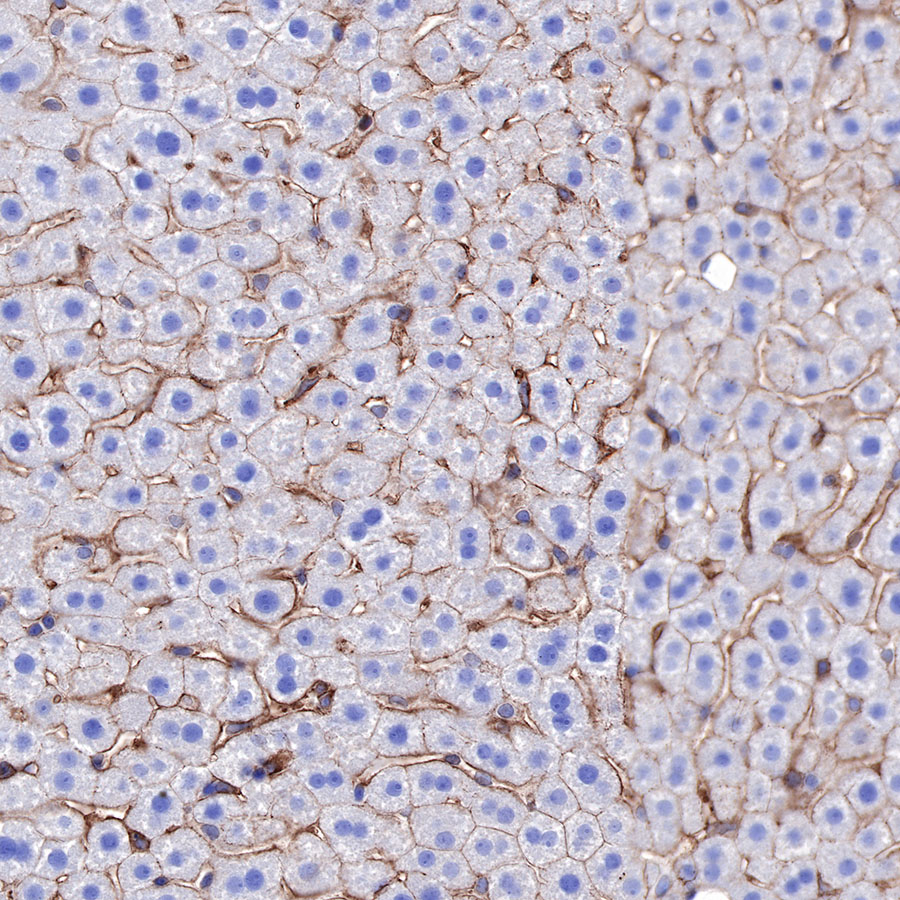

IHC shows positive staining in paraffin-embedded mouse kidney. Anti-α-Actinin-1 antibody was used at 1/2000 dilution, followed by a HRP Polymer for Mouse & Rabbit IgG (ready to use). Counterstained with hematoxylin. Heat mediated antigen retrieval with Tris/EDTA buffer pH9.0 was performed before commencing with IHC staining protocol.

IHC shows positive staining in paraffin-embedded mouse liver. Anti-α-Actinin-1 antibody was used at 1/2000 dilution, followed by a HRP Polymer for Mouse & Rabbit IgG (ready to use). Counterstained with hematoxylin. Heat mediated antigen retrieval with Tris/EDTA buffer pH9.0 was performed before commencing with IHC staining protocol.